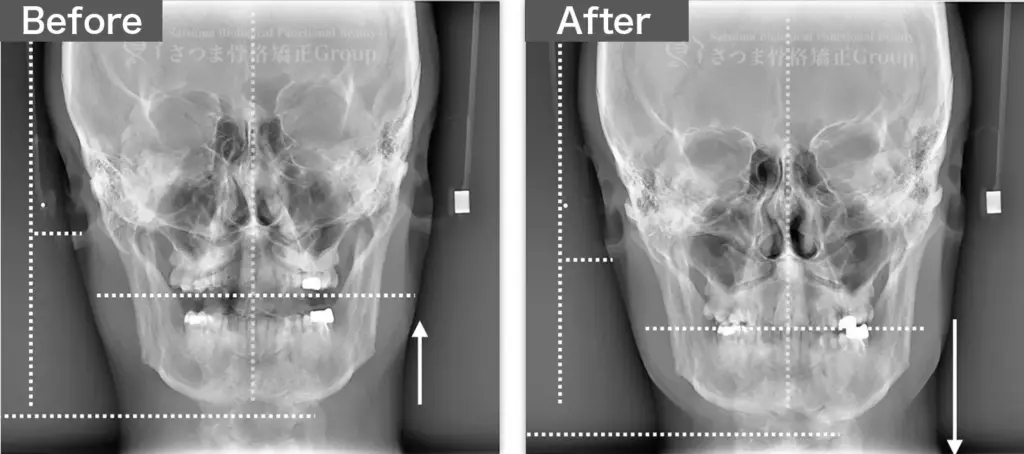

BEFORE

軽度の顎変形症あり

下顎の左方シフト

頚椎の斜頸

中顔面の滑落

Mild jaw deformity present

Leftward shift of the mandible

Cervical spine torticollis

Sagging of the midface

AFTER

下顎の正中誘導

頚椎の斜頸矯正

中顔面の短縮

Midline correction of the mandible

Correction of cervical spine torticollis

Shortening of the midface